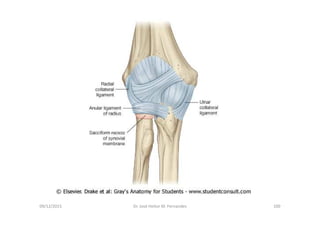

Anatomia do cotovelo (vista lateral)

Ligamento colateral ulnar- cotovelo

Ligamento colateral ulnar ( em flexão)